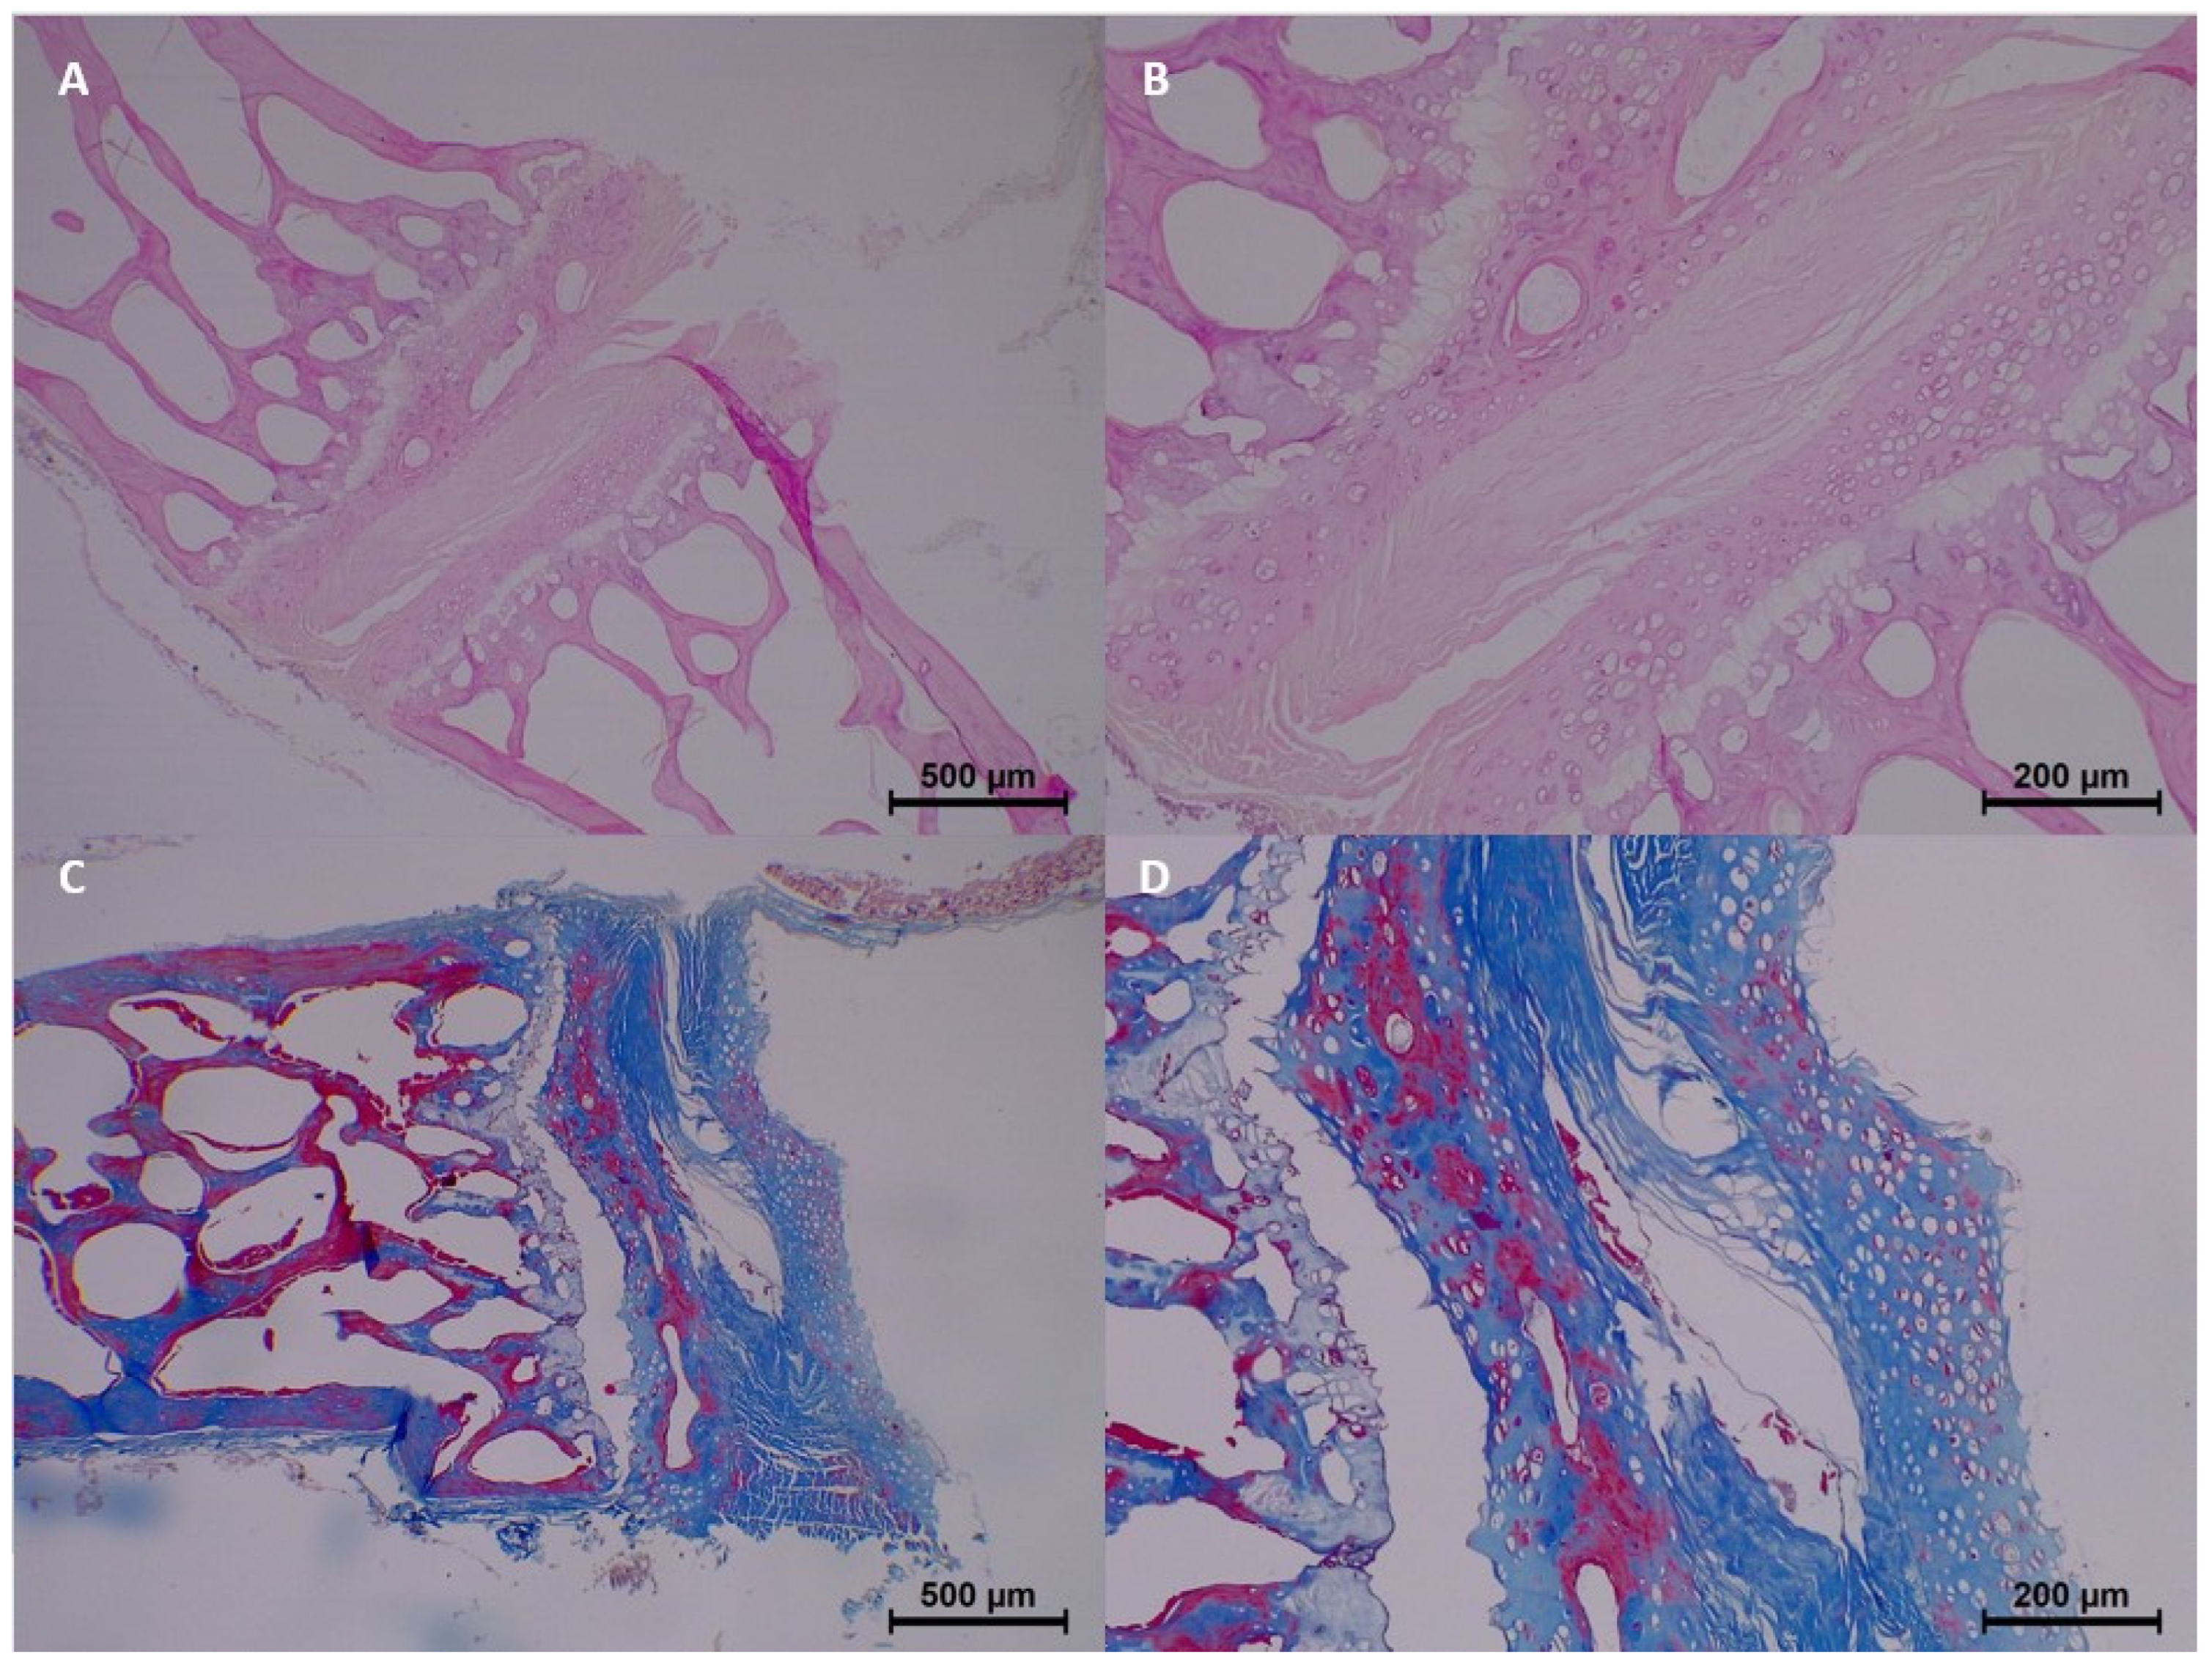

At 30 days postmortem, histopathological changes became more advanced. Homogenization was moderate to common, and eosinophilia was moderate in three samples. Dissociation of the epithelium and connective tissue became more distinct, with four samples exhibiting moderate dissociation. Degeneration and pyknosis also increased, with common degeneration noted in one sample and moderate pyknosis observed in three samples. Collagen changes intensified, with moderate collagen fragmentation seen in two samples (

Table 3 and

Figure 5).